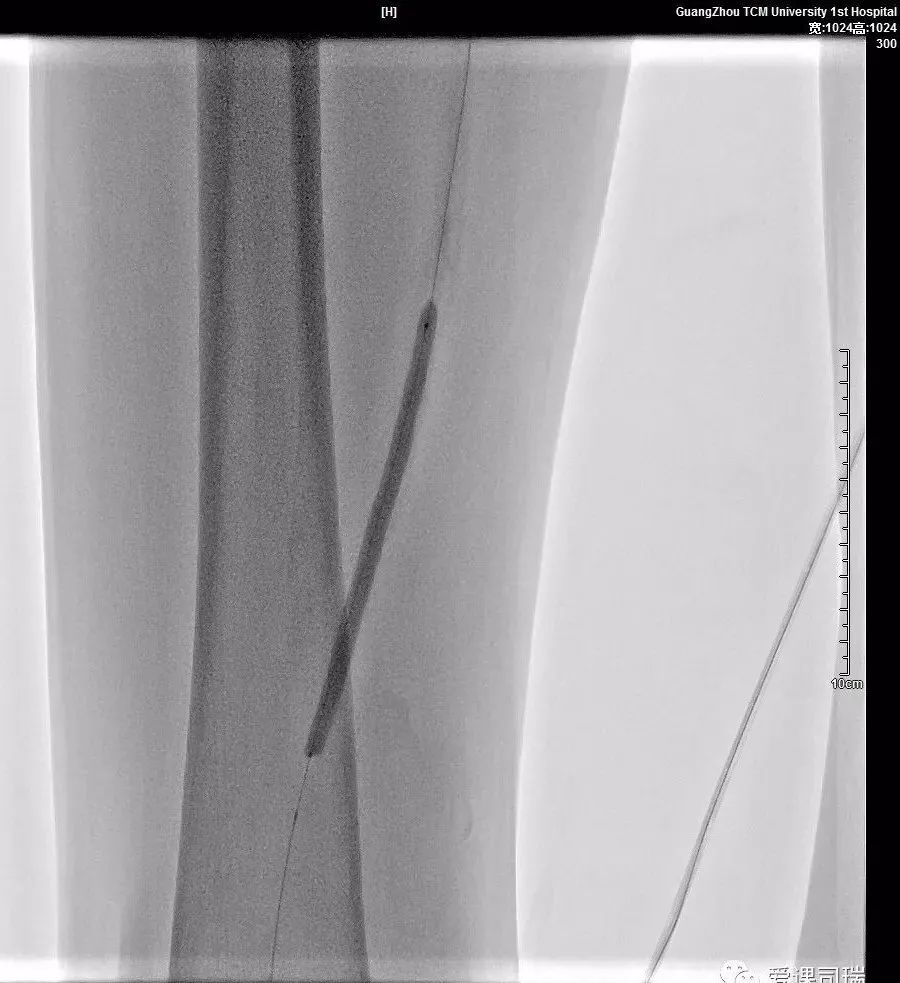

a.白箭处为右股浅动脉起始部闭塞;b.导管鞘(粗白箭)支撑导管(细白箭)并配合导丝(黑箭)开通闭塞;

图中的黑长条就是球囊导管正在对狭窄血管进行扩张成形